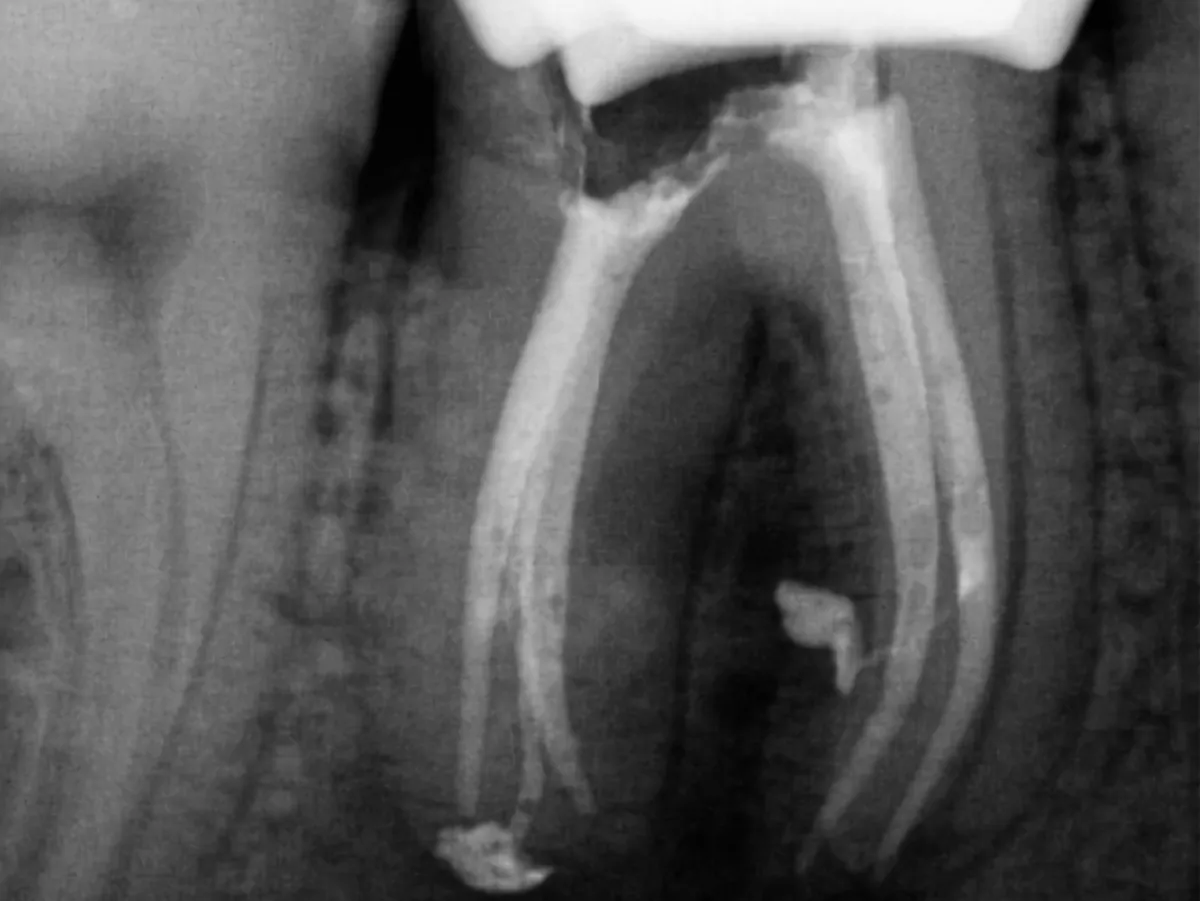

W każdy czwartek o 19:00 otrzymujesz omówienie najciekawszego przypadku endodontycznego z minionego tygodnia. RTG po, problem, jaki zastałam, zastosowane rozwiązanie i praktyczny wniosek.

Rozpisane krok po kroku: na co zwrócić uwagę w diagnostyce radiologicznej i jakie ma ona odzwierciedlenie w rzeczywistości pod mikroskopem.